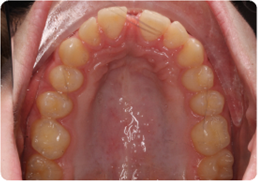

Each case shows the front view and an arch or side view, before and after BioLign Method-guided treatment.

Misaligned lower arch corrected with coordinated expansion